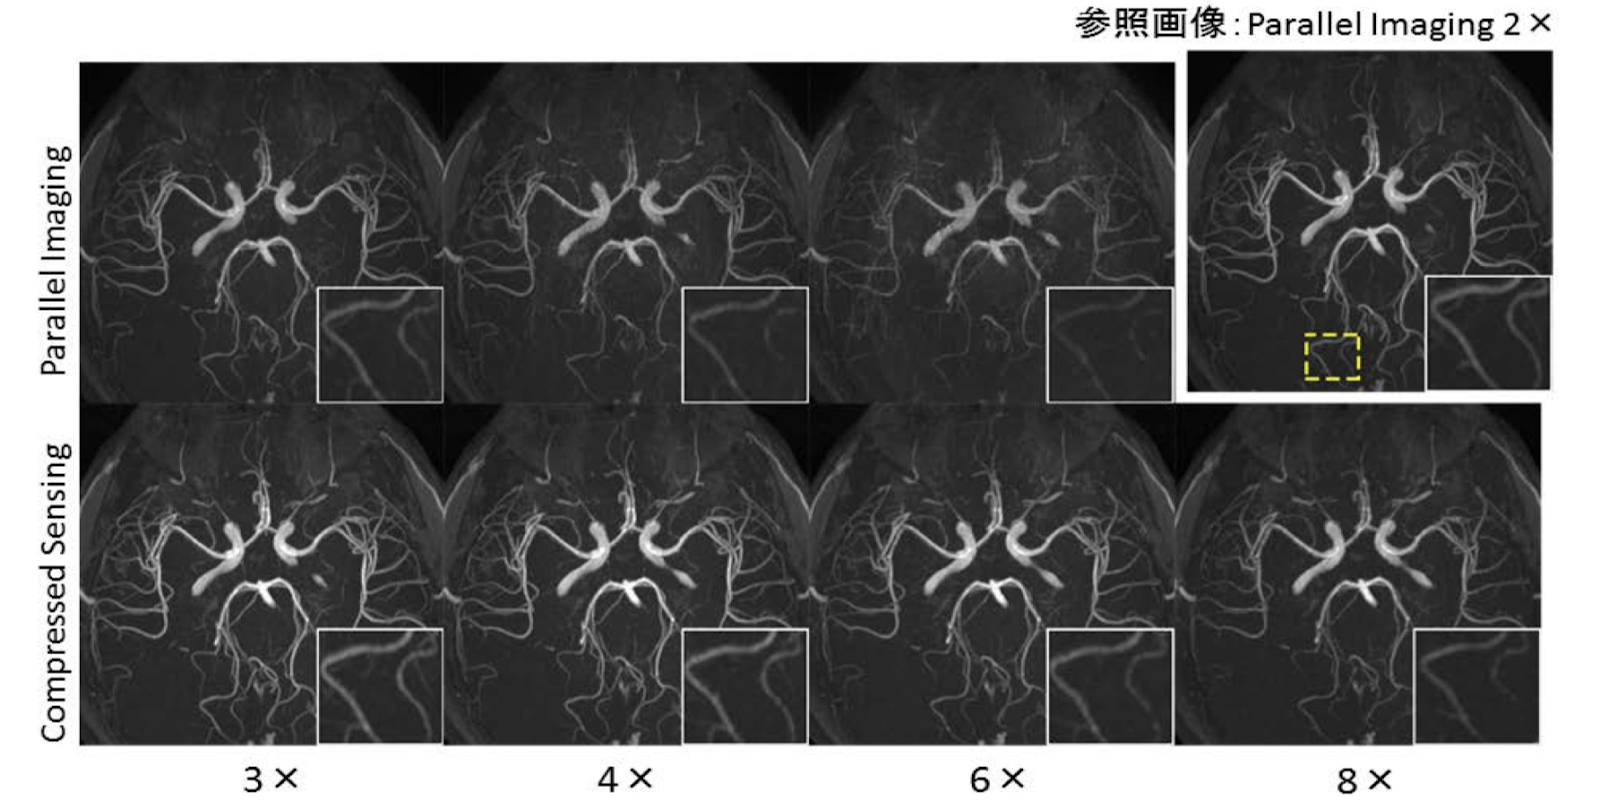

例えば、医療現場に必須とも言える検査の手法であるMRI撮像が挙げられます。MRIは検査に有用なものではありますが、安静にしておかなければならない時間が長いという問題点があります。そこでMRIに撮像時間を短縮するという試みが行われていますが、その中でスパースモデリングを利用した手法が期待されています。データを間引くことで撮影時間を短縮したとしても、スパースモデリングを利用することで診断に十分な鮮明さを担保することができるのです。下図は既存手法(上段)とスパースモデリングで再構成した画像(下段)の比較ですが、スパースモデリング を用いた画像再構成のほうが撮像の高速化倍率を高くした時により鮮明な画像を作成できていることがわかります(図下部の数値が高速化の倍率を示します)。

従来法とスパースモデリングによる画像の再構成の結果(出典元:T. Yamamoto, et al. Invest Radiol (2016))